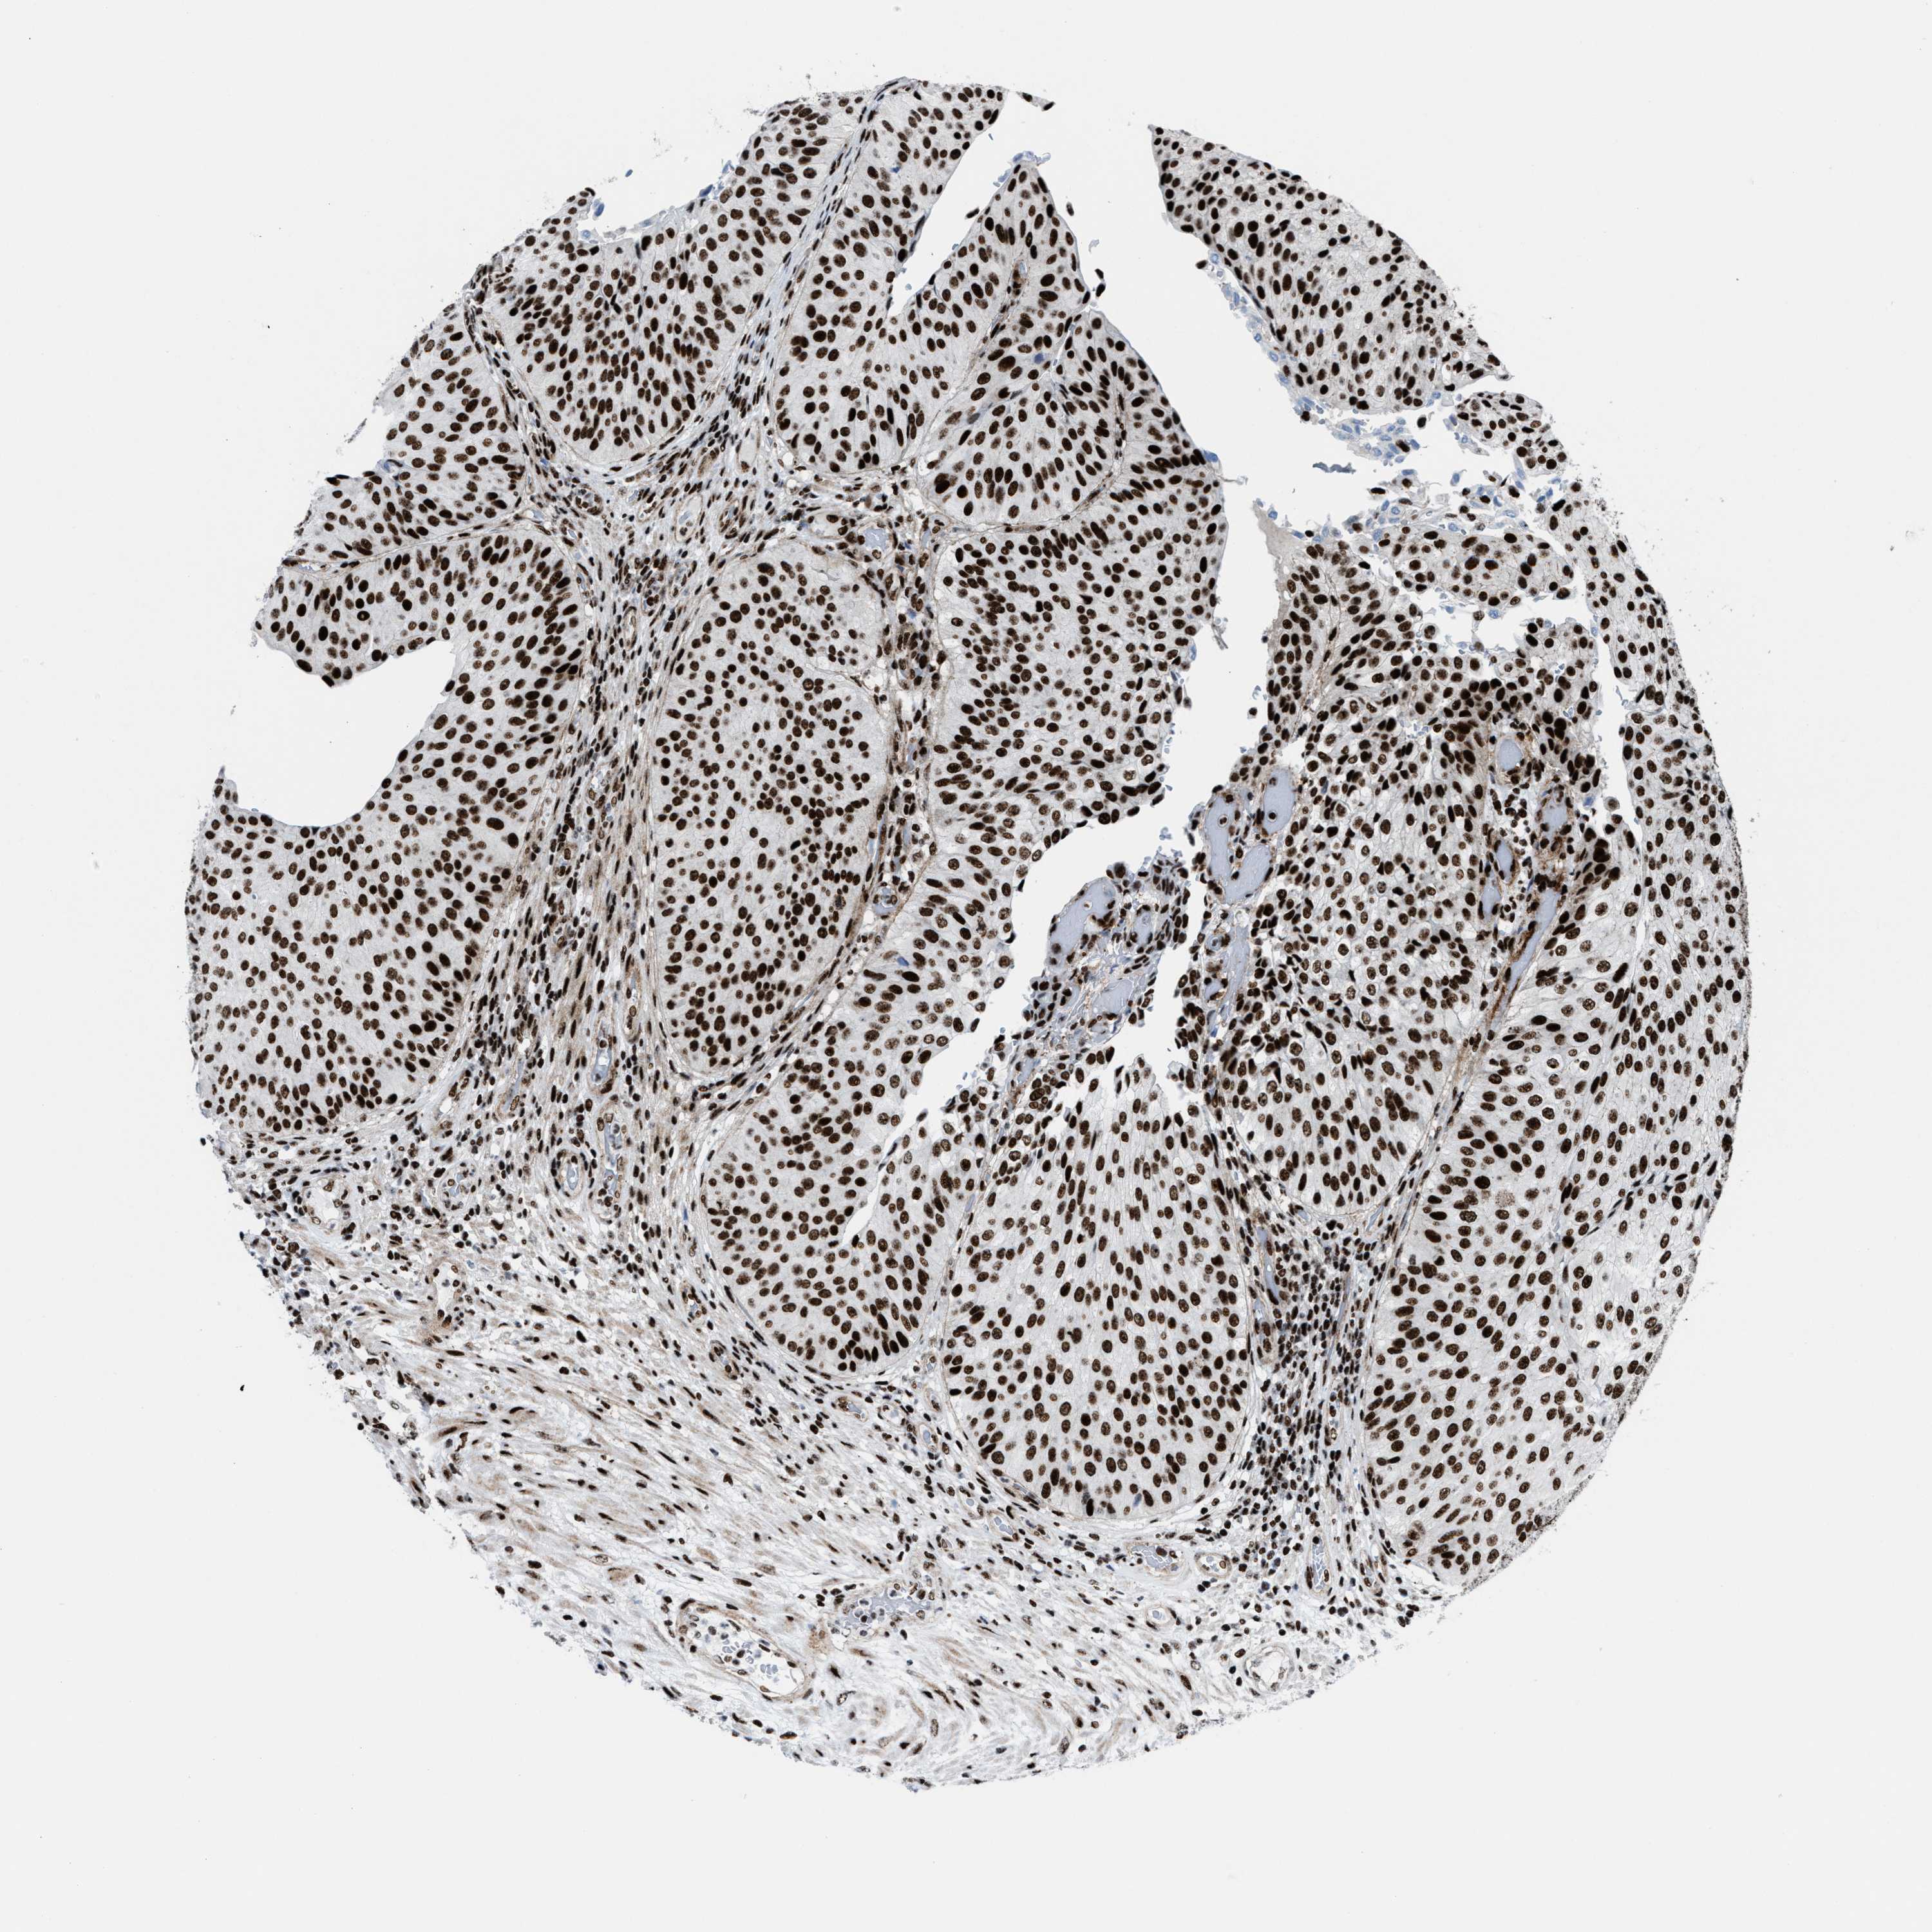

UROTHELIAL CANCER - Protein expressioni

A mouse-over function shows sample information and annotation data. Click on an image to view it in a full screen mode. Samples can be filtered based on level of antibody staining by selecting one or several of the following categories: high, medium, low and not detected. The assay and annotation is described here.

Note that samples used for immunohistochemistry by the Human Protein Atlas do not correspond to samples in the TCGA dataset.

Antibody stainingi

Antibody staining in the annotated cell types in the current human tissue is reported as not detected, low, medium, or high, based on conventional immunohistochemistry profiling in selected tissues. This score is based on the combination of the staining intensity and fraction of stained cells.

Each image is clickable and will lead to virtual microscopy that enables deeper exploration of all samples and also displays staining intensity scores, fraction scores and subcellular localization as well as patient and tissue information for each sample.

Antibody HPA054094

Antibody HPA054559

Antibody CAB022069

Staining

High

Medium

Low

Not detected

Intensity

Strong

Moderate

Weak

Negative

Quantity

>75%

75%-25%

<25%

None

Location

Nuclear

Cytoplasmic/membranous

Cytoplasmic/membranous,nuclear

Urothelial carcinoma, High grade

Urothelial carcinoma, NOS

Urothelial carcinoma, Low grade